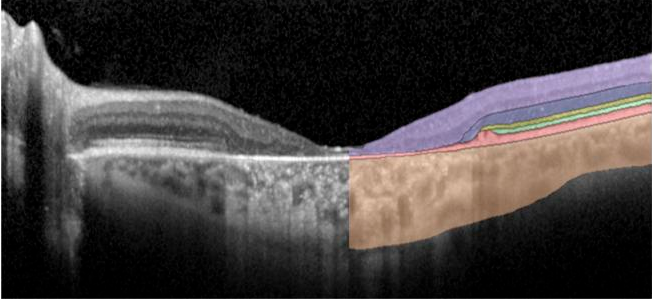

Spectral-domain optical coherence tomography uses light to image layers of the retina. Image Courtesy of: Brian P. Brooks, M.D., Ph.D. and Brett G. Jeffrey, Ph.D.